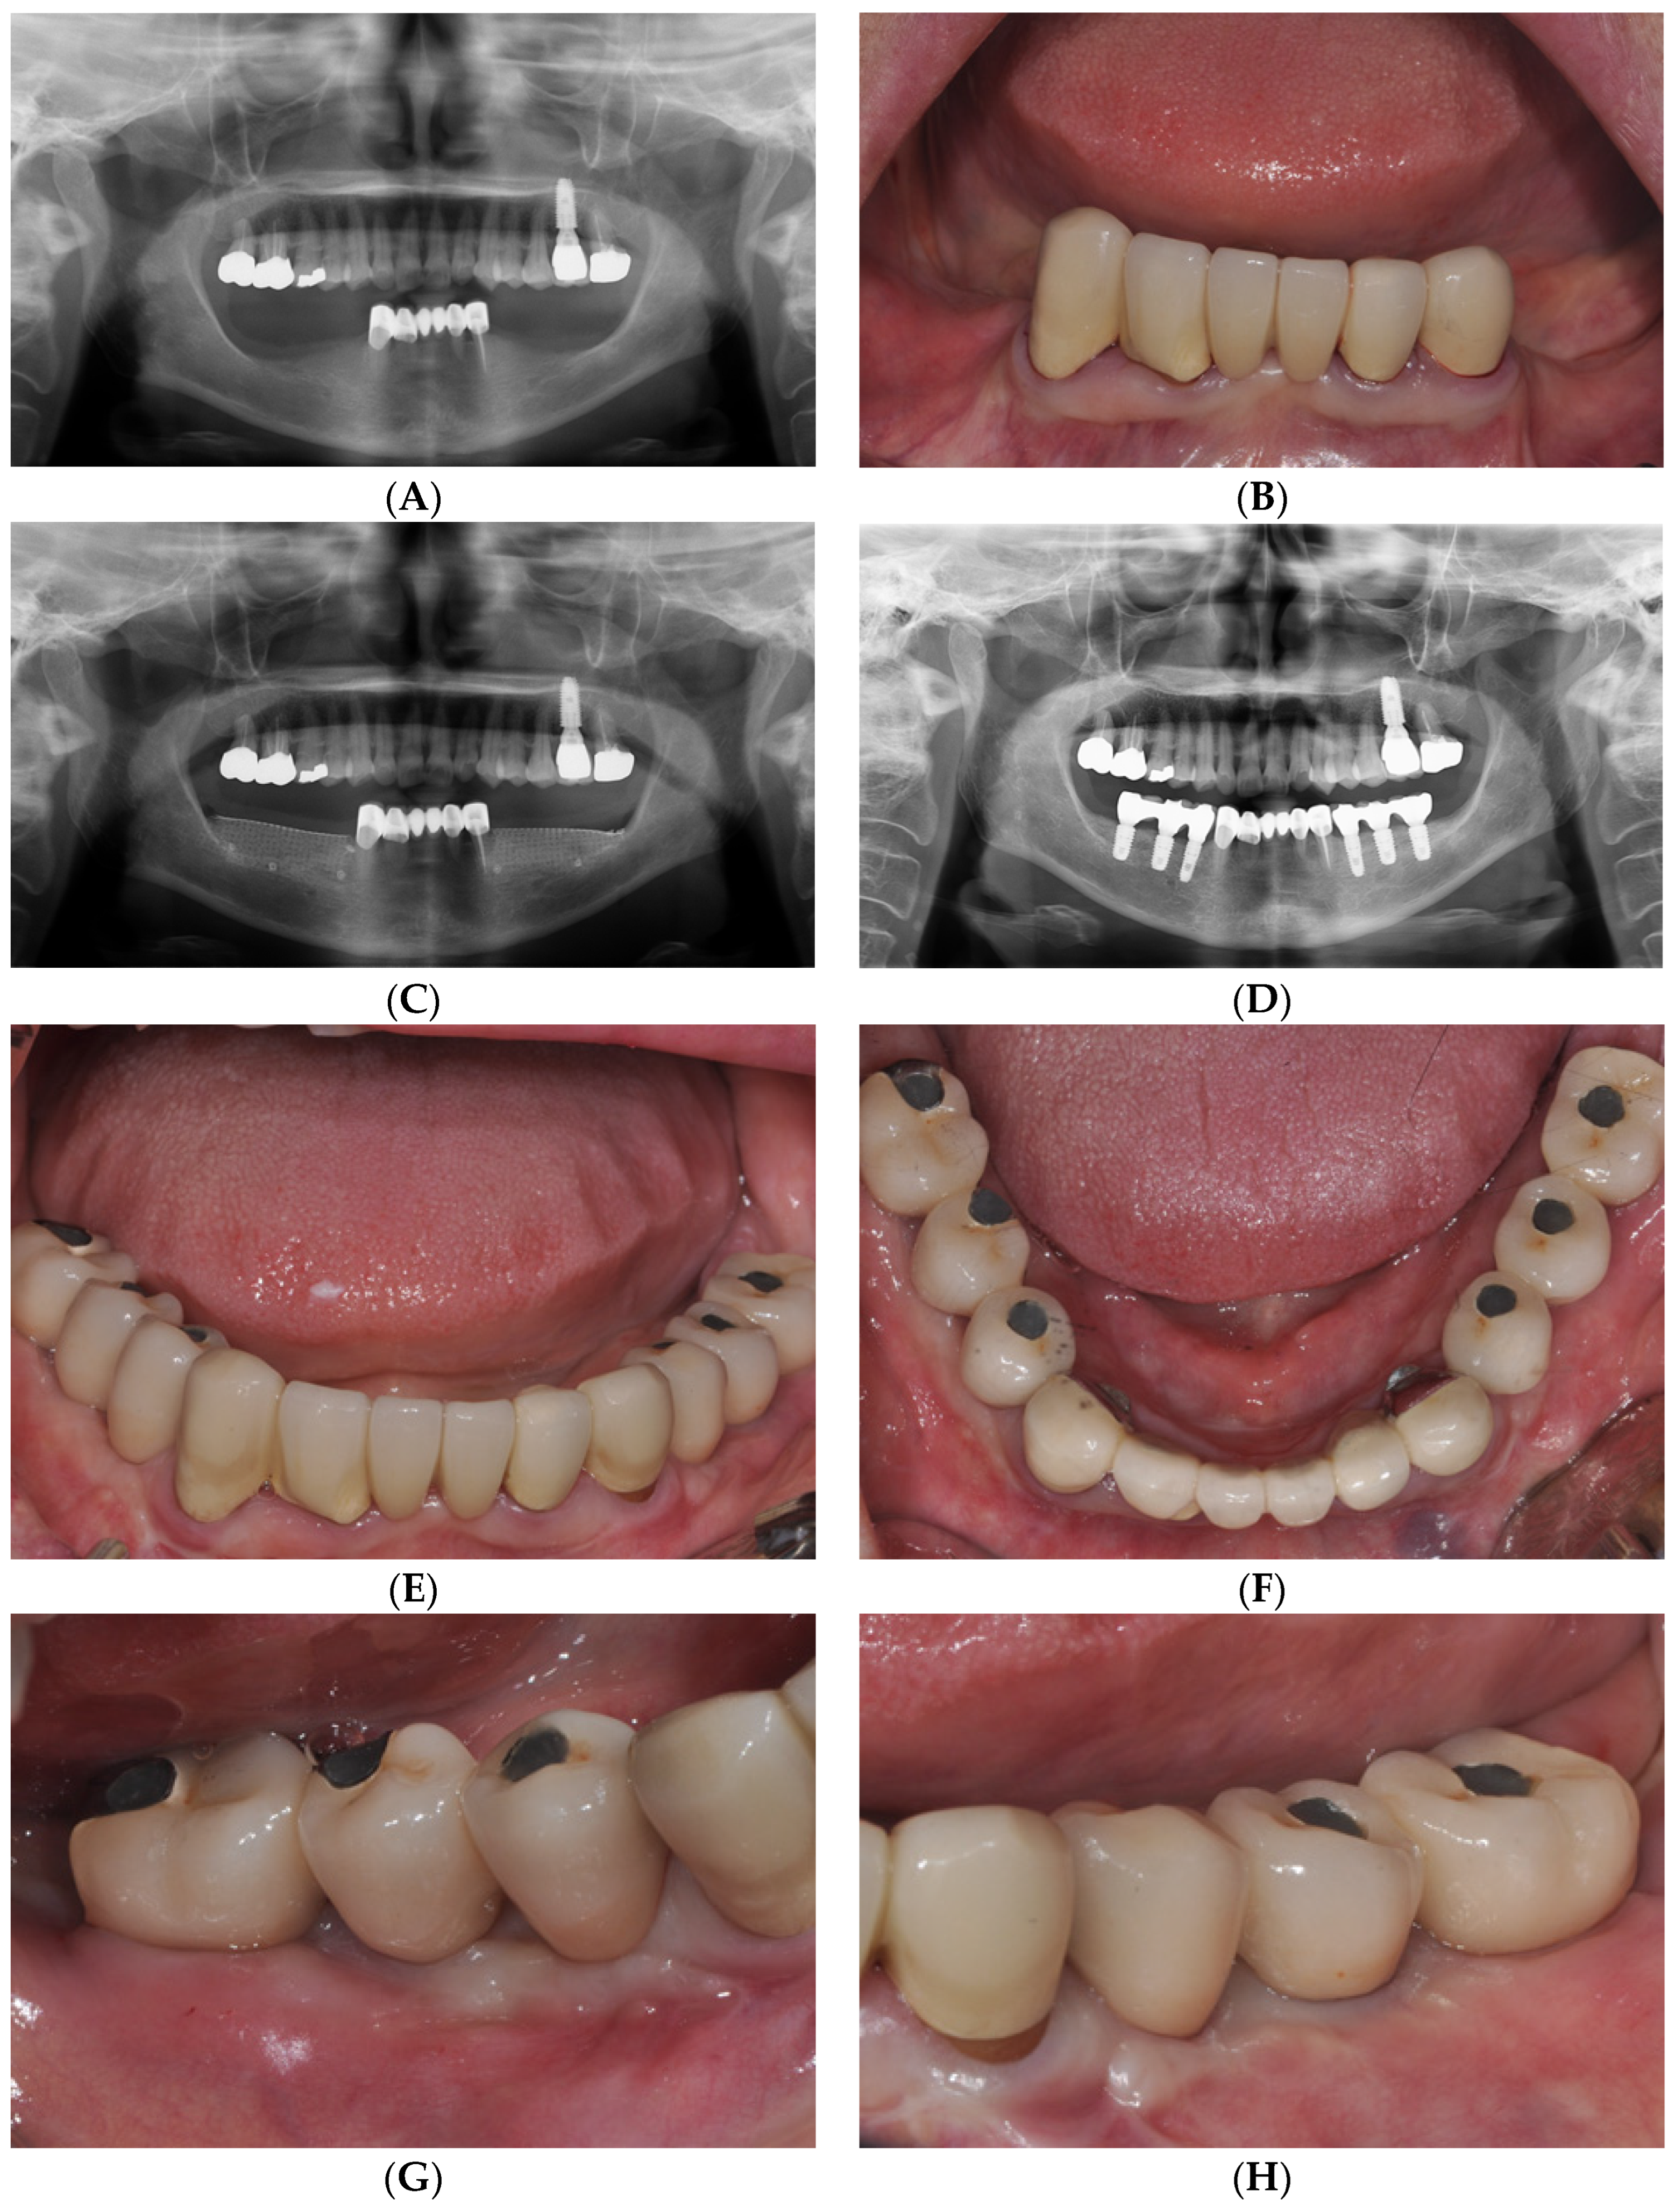

2.2. Case